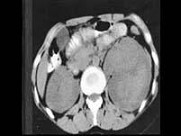

- 多项选择题女,26岁, 临床诊断为绒毛膜癌,行经腹子宫全切术后1月, CT检查如图所示,下列说法正确的是 ( )

A、左肾周可见低密度区,增强后无强化,其内有散在的片状稍高密度影

D、考虑为绒毛膜癌肾转移

E、合并有左肾周自发性血肿